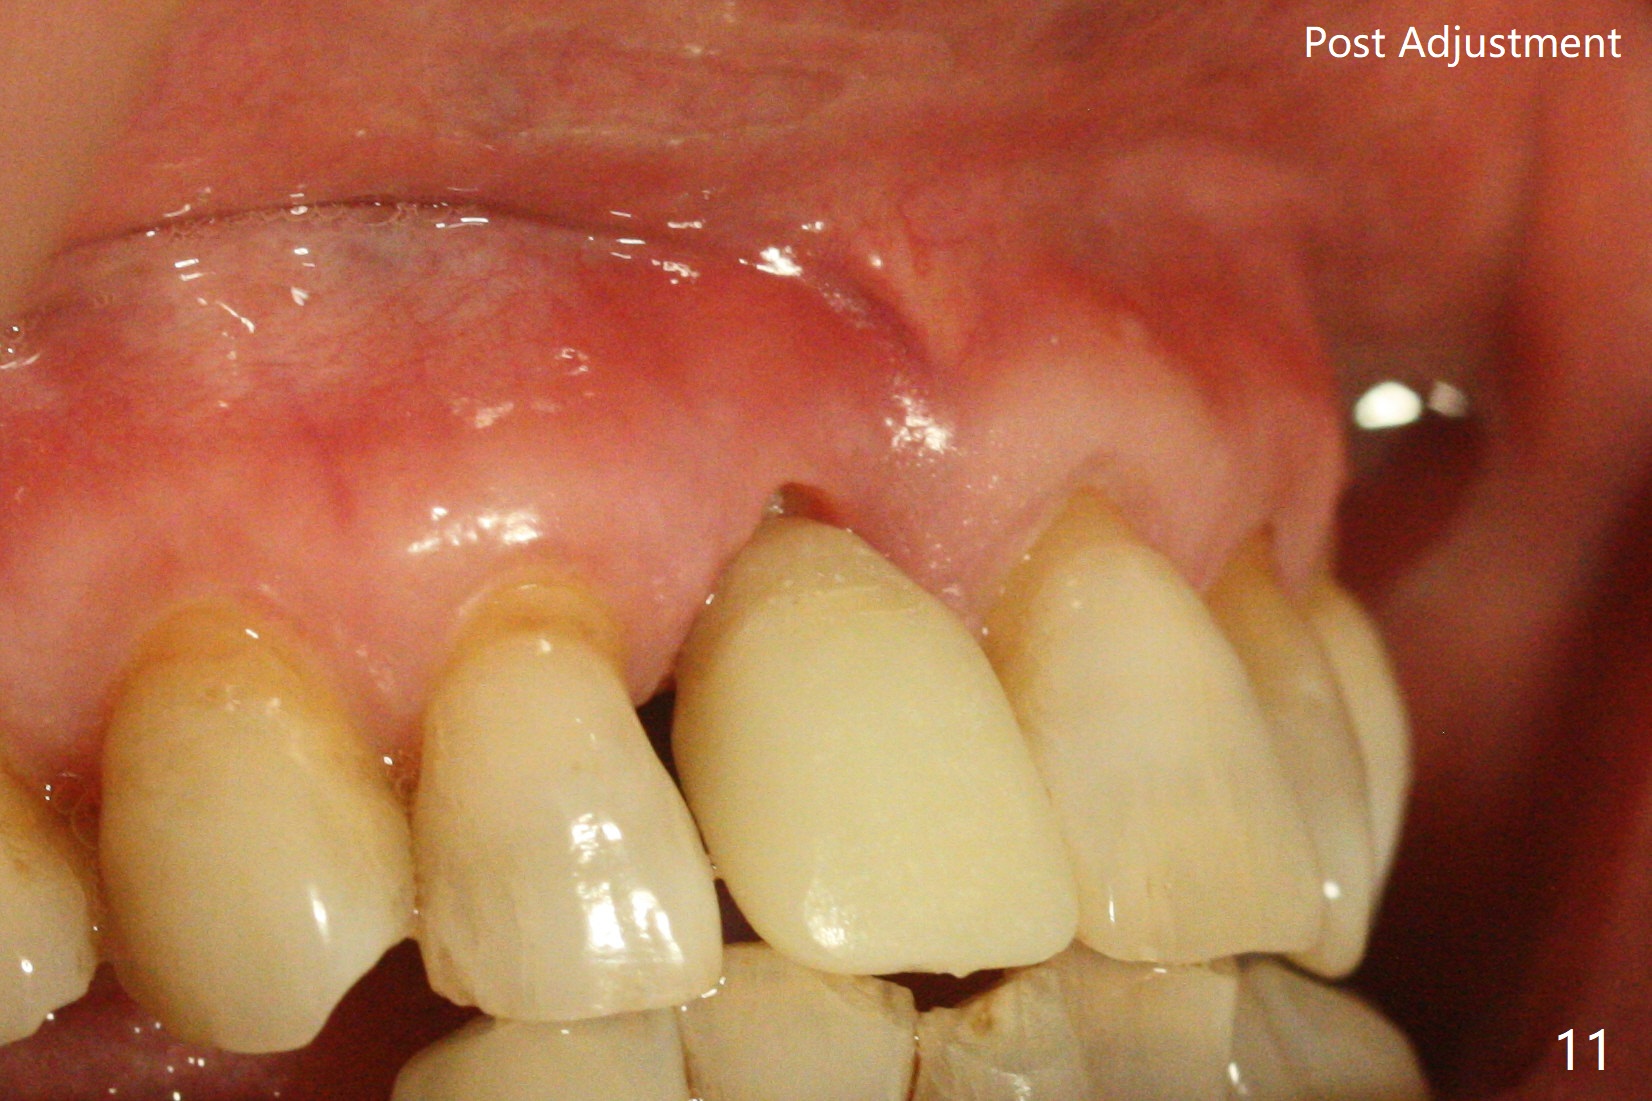

59岁女术前右下1,2切缘磨短后,右上1颊侧移位得到纠正(图一(咬合创伤))。拔牙后证实颊侧骨板缺失,钻洞始于腭侧(图二),当1.5毫米钻头感觉刚穿破鼻底时,置入2.5x14(4)毫米一段式植体,好像进入鼻腔,但是扭力<10Ncm(图三)。把一张PRF膜放入牙槽窝,一端紧贴颊侧牙龈腭侧,另一端放置颊侧牙龈颊侧(图四),然后开始用粘性骨粉(图五,七:*(100%皮质骨))充填颊侧间隙。后者填满时(图五:*),将外面一端PRF翻转覆盖牙槽窝开口,并插入基台固定(图六),最后插入龈下,用临时牙冠固定(图八(T),九(*:PRF))。术后九天牙龈退缩(图十:^),临时牙冠突出(*),后者龈缘和切缘进行调整,缩短(图十一,十二),少许骨粉暴露(图十二:>),十四天后牙龈往下生长,好像形成角化龈(图十三:*)。